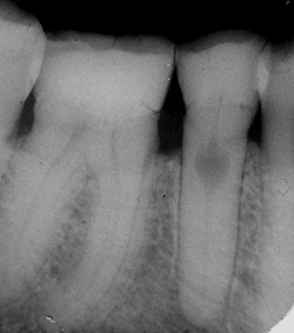

what is the diagnosis?

regional odontodysplasia